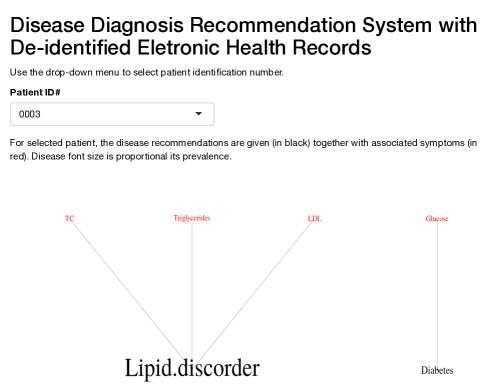

We identify additional 10 latent diseases with prevalence of 493, 218, 192, 174, 114, 82, 64, 24, 15, and 15 patients. Some of the latent diseases are quite interesting. Latent disease 1 is lipid disorder, associated with high total cholesterol (TC), triglycerides and low density lipoprotein (LDL). Cholesterol is an organic molecule carried by lipoproteins. LDL is one type of such lipoproteins, commonly referred to as “bad” cholesterol. At normal levels, TC and LDL are essential substances for the body. However, high levels of TC and LDL put patients at increased risk for developing heart disease and stroke. Triglycerides are a type of fat found in the blood which are produced by the body from excessive carbohydrates and fats. Like cholesterol, triglycerides are essential to life at normal levels. However, a high level is associated with an increased chance for heart disease.

6.3 A Web application for disease diagnosis

A good user interface is critical to facilitate the implementation of the proposed approach in the decision process of healthcare providers, and for broad application. Using the R package shiny (Chang et al. , , 2015), we have created an interactive web application (available at https://nystat3.shinyapps.io/Rshiny/). The application displays disease diagnosis recommendations for de-identified patients selected by the user. We show the application for two patients in Figure 6.